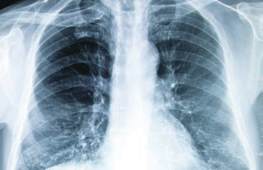

Lungenentzündungen haben

viele Ursachen

Immer noch sind Lungenentzündungen unter den Infektionskrankheiten die häufigste Todesursache in

unseren Breiten. Oftmals entstehen sie durch Pneumokokken, aber auch durch Viren oder Pilze.

Lungenentzündungen sind unter den Infektionskrankheiten immer noch

die häufigste Todesursache.